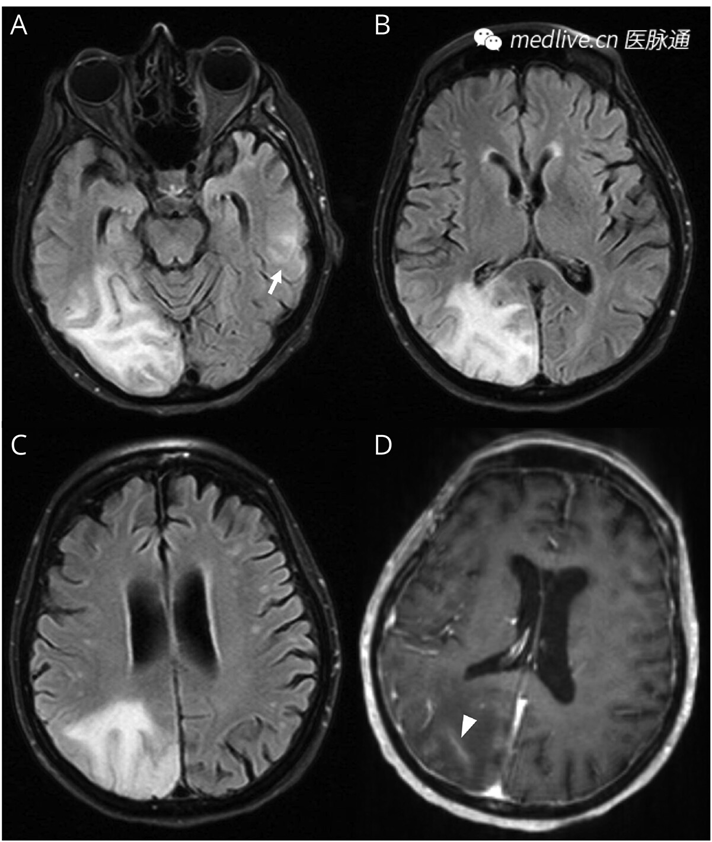

脑部MRI:右侧颞枕区有较大的T2高信号,并伴有软脑膜强化。弥散加权成像(DWI)和磁敏感加权成像(SWI)未见急性梗死或颅内出血(图1)。

图1 脑部MRI

轴位FLAIR MRI显示,右侧颞枕区皮质下白质内存在一个融合性T2高信号病灶,并延伸至皮质-皮质下交界处(A–C)。左侧颞叶内可见一个较小的T2高信号区域(A,箭头)。轴位T1加权增强MRI显示,病灶周围存在血管源性水肿

及软脑膜强化(D,箭头)。DWI和SWI未检测到异常。